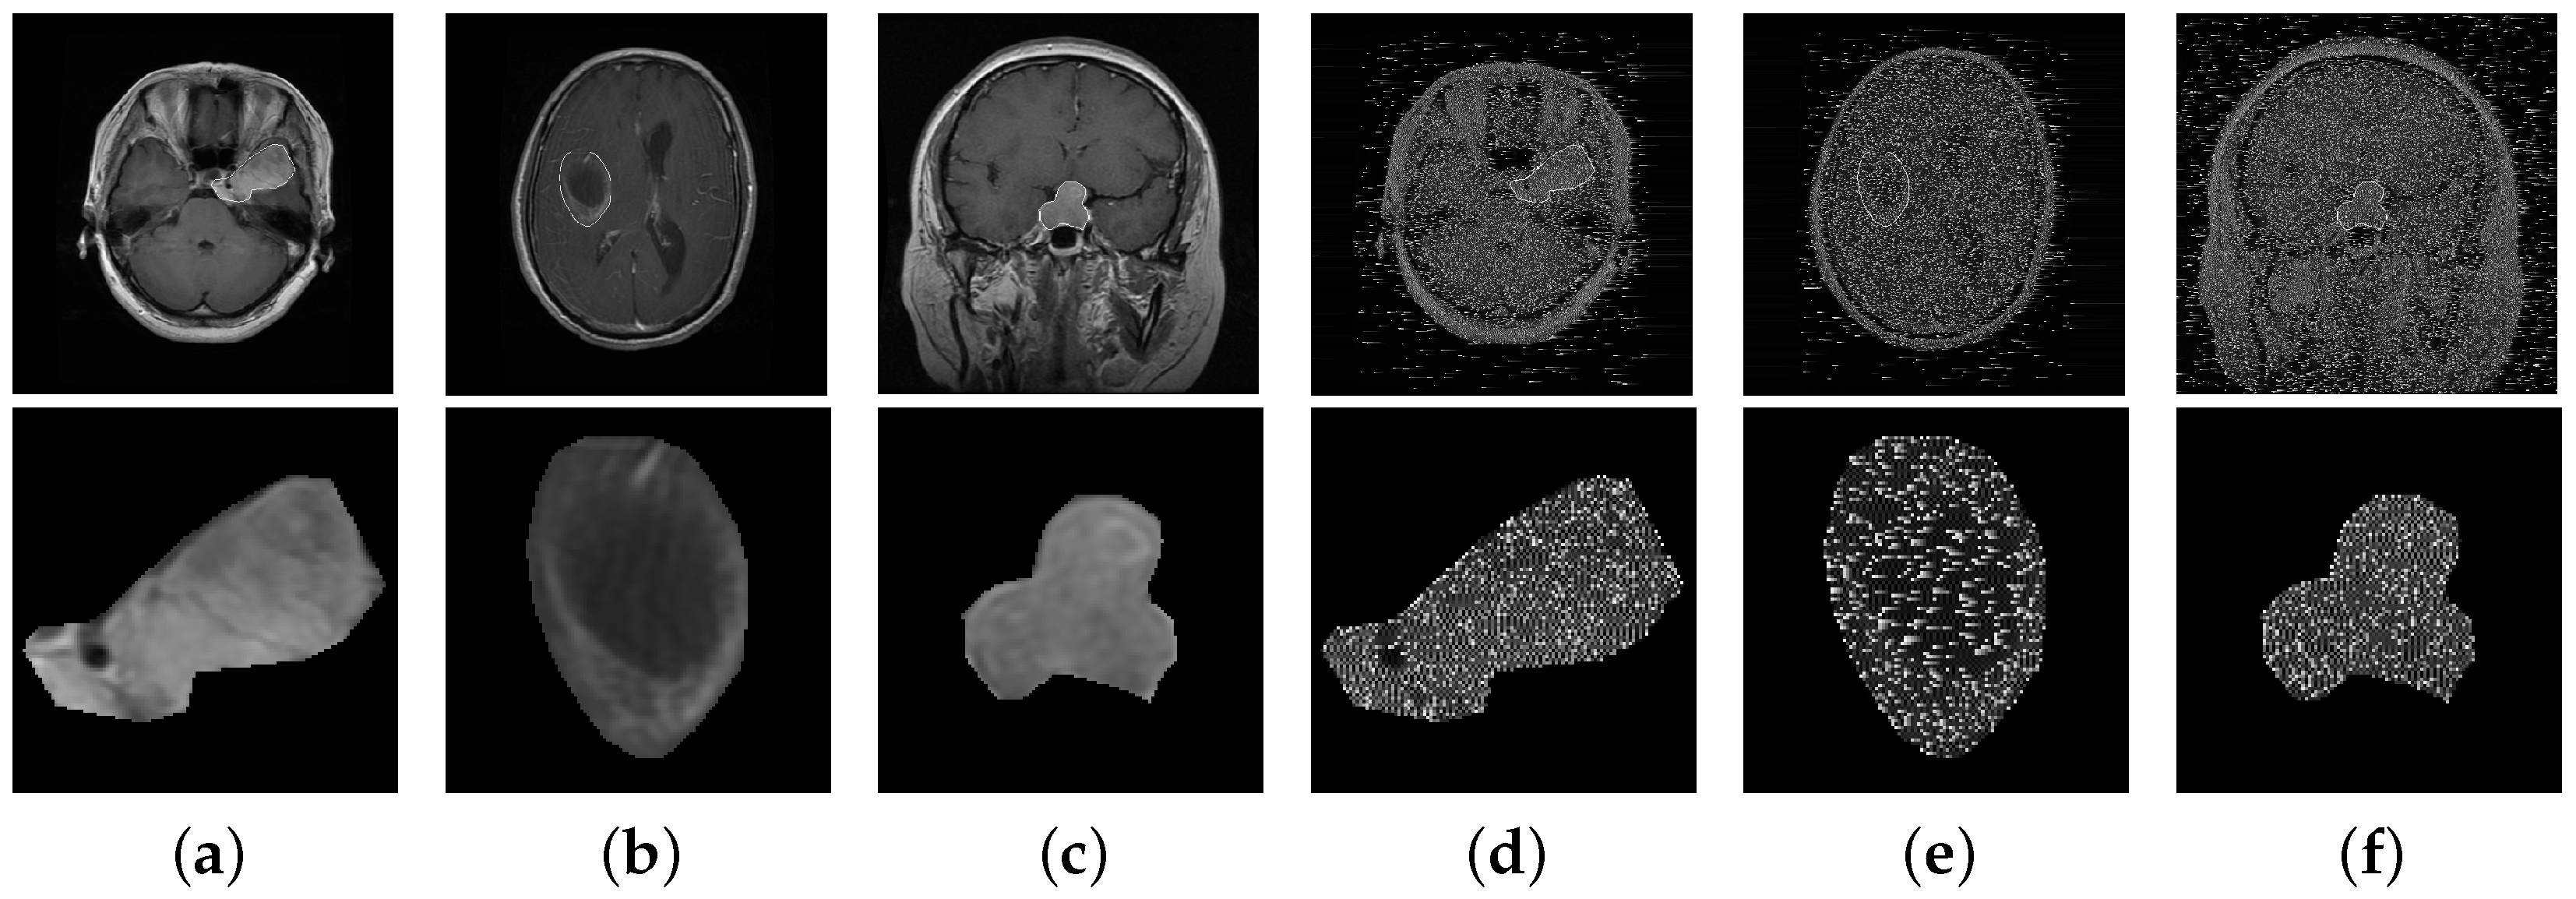

- Dataset. Although different medical image modalities, such as Positron Emission Tomography (PET), Computed Tomography (CT), and Magnetic Resonance Imaging (MRI) scans can be used to create images of the brain, MRI remains the primary diagnostic modality for brain tumors because it is highly sensitive in visualizing soft tissues within the brain compared with other modalities. Therefore, we used an MRI dataset in our experiments. It is worth mentioning that our proposed secure retrieval scheme can be readily implemented for other types of image modalities. In simulations, we evaluated the performance of different brain tumor retrieval schemes on a public brain tumor MRI dataset available from [3]. This dataset contains 3064 T1-weighted, contrast-enhanced images in size from 233 patients with three kinds of brain tumors: meningioma (708 slices), glioma (1426 slices), and pituitary (930 slices). The images in the dataset were split into five subsets for fivefold cross-validation. Among these subsets, one was used as query images, while the rest of them were used as template images. Also, it was ensured that slices from the same patient did not appear simultaneously in the template and query images. Figure 4 shows an example image from the dataset for each brain tumor type in plain and encrypted form. The cipher images were obtained by encrypting the plain images using our proposed PE algorithm. In the cipher images, pixel values which were substituted during encryption appear as white noise for the key value in Equation (6).

Figure 4. Example images from the dataset for each brain tumor type. (a–c) Plain-images and (d–f) their corresponding cipher images obtained from our proposed encryption technique. The tumor region (ROI) in each image is enlarged and shown below it. This information is visually unrecognizable in the cipher images.Figure 4. Example images from the dataset for each brain tumor type. (a–c) Plain-images and (d–f) their corresponding cipher images obtained from our proposed encryption technique. The tumor region (ROI) in each image is enlarged and shown below it. This information is visually unrecognizable in the cipher images.